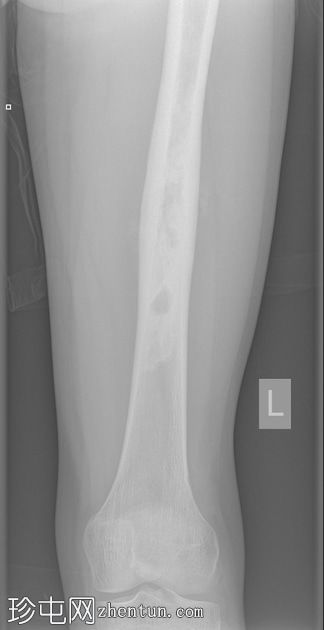

X光片

正面

侧面

斜面

左股骨中段可见边界不清的硬化区域,伴有宽阔的过渡区和虫蛀状外观。

邻近软组织可见小块钙化灶。无骨折或脱位。